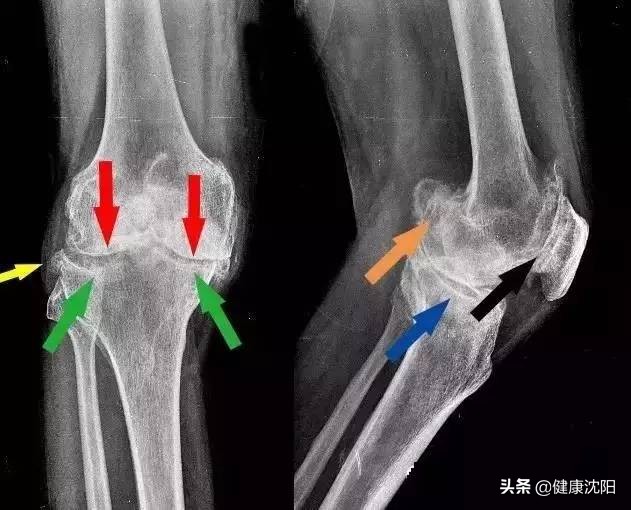

“骨刺”的医学称谓是“骨质增生”,也可以称为“骨赘”,是随年龄增长骨骼老化、退变的必然征象。成年以后几乎所有人都会发生。骨质增生其实是关节退变(又称骨关节炎)的表现之一。随着年龄的增长,几乎所有人都不可避免地会出现骨质增生和骨关节炎,其中以膝关节、手部关节以及颈椎和腰椎最为多见。如前所述,骨质增生其实是人体针对关节退变、稳定性下降所产生的一种“代偿性”保护措施,是人体应对关节退变、不稳定而产生的保护性措施。某种程度上讲,这是人体的一种“保护”策略。